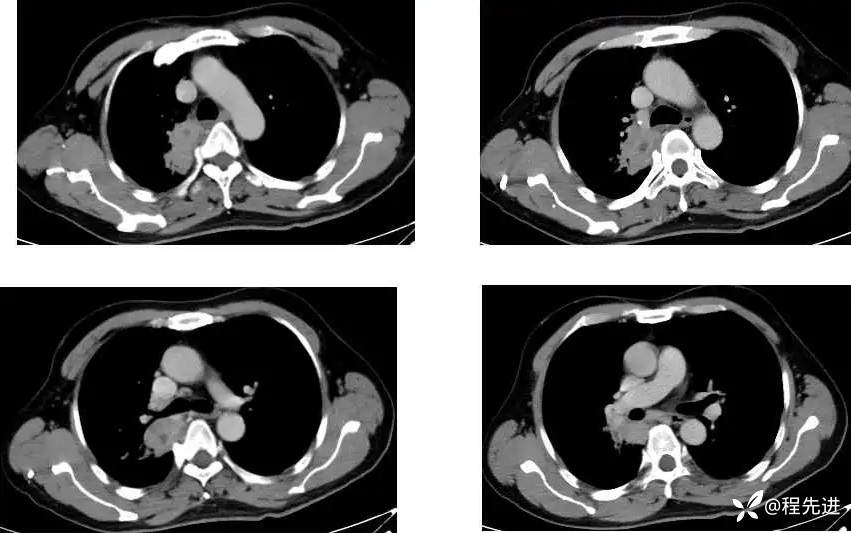

主 诉:间断咳嗽、痰中带血1月,发现肺门占位8天

现病史:患者1月前受凉后出现咳嗽咳痰,痰中见血丝,量少,伴有右侧胸痛不适,夜间有盗汗,无发热,在社区予以抗感染治疗3天(具体用药不详),胸痛症状缓解,但仍间断出现痰中带血,未再行诊治;8天前检查发现肺门占位;患者近2日咯血量较前增多,每日约4-5口,为鲜红色

CT增强:

MR平扫+增强: